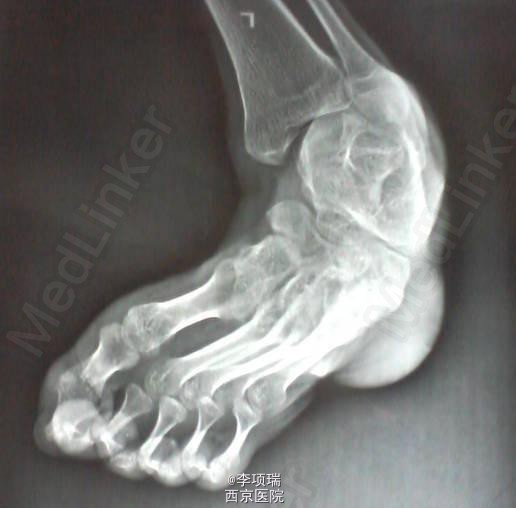

周末病例讨论:一例严重的马蹄内翻足畸形

患者,27岁男性,5.6岁前走路正常,后因先天性骶脊膜膨出,行手术治疗后,其后几年逐渐出现,马蹄内翻畸形(估计是脊髓栓系综合征所致),合并脊柱侧弯畸形;一直没有治疗,现在出现严重马蹄内翻畸形,走路时,足背着地导致足背经常溃烂,现在患者想,改善外观,用足底着地,今天将图片,发出来请大家讨论,有没有,手术指征,以及怎样设计手术方案?